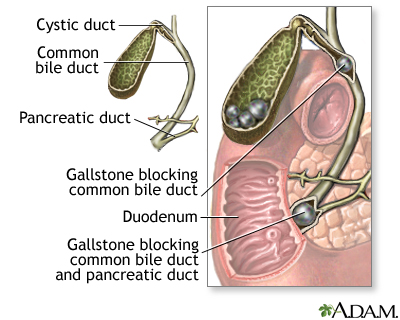

Choledocholithiasis (Common Bile Duct Stones)

Gallstones can also be present in the common bile duct, rather than the gallbladder. This condition is called choledocholithiasis.

- In most cases, common bile duct stones are secondary (they form in the gallbladder and pass into the common duct). About 10% of patients having surgery for gallstones have common bile duct stones at the same time.

- Less often, the stones form in the common duct itself. They are more likely to cause infection than secondary common duct stones.

Symptoms of Stones in the Common Bile Duct (Choledocholithiasis)

Stones lodged in the common bile duct can cause symptoms that are similar to those produced by gallbladder stones. But they may also cause symptoms such as:

- Jaundice (yellowish skin).

- Dark urine, lighter stools, or both.

- Fever, chills, nausea and vomiting, and severe pain in the upper right abdomen. These symptoms suggest an infection in the bile duct (called cholangitis).

- Rapid heartbeat and abrupt blood pressure drop.

As in acute cholecystitis, patients who have these symptoms should seek medical help immediately. They may require emergency treatment.

Gallstones, however, can cause an obstruction at any point along the ducts that carry bile. In such cases, symptoms can develop.

- In most cases of obstruction, the stones block the cystic duct, which leads from the gallbladder to the common bile duct. This can cause pain (

biliary colic

), infection and inflammation (acute cholecystitis

), or both. - About 10% of patients with symptomatic gallstones also have stones that pass into and obstruct the common bile duct (

choledocholithiasis

).

Infection in the common bile duct from blockage is common and serious. If antibiotics are administered immediately, the infection clears up in 75% of patients. If cholangitis does not improve, the infection may spread and become life-threatening. Either surgery or a procedure known as endoscopic sphincterotomy is required to open and drain the ducts.Pancreatitis.

Common bile duct stones are responsible for most cases of pancreatitis (inflammation of the pancreas), a condition that can be life-threatening. The pancreatic duct, which carries digestive enzymes, joins the common bile duct right before it enters the intestine. It is therefore not unusual for stones that pass through or lodge in the lower portion of the common bile duct to obstruct the pancreatic duct.